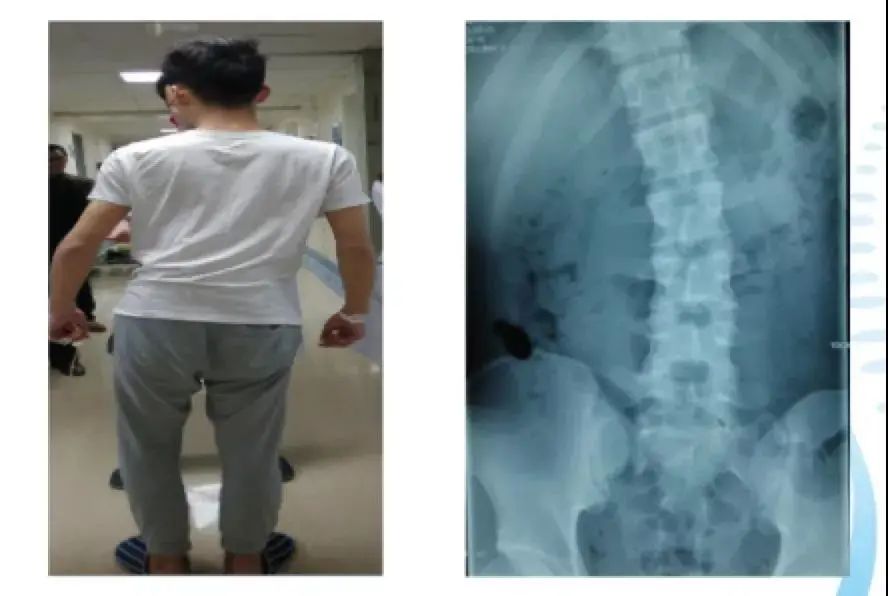

广州一名18岁女孩小邹常出现腰痛、脖子酸等症状。到医院就诊时,医生发现,她的腰椎向右侧弯、旋转,脊柱也向右发生明显侧弯。

长期的固定单方向睡姿,使得小邹的脊柱体态逐渐失衡,骨盆发生旋移、腰椎出现旋转,最终导致小邹出现脊柱侧弯,这也是引起她腰酸、颈发酸的主要原因。